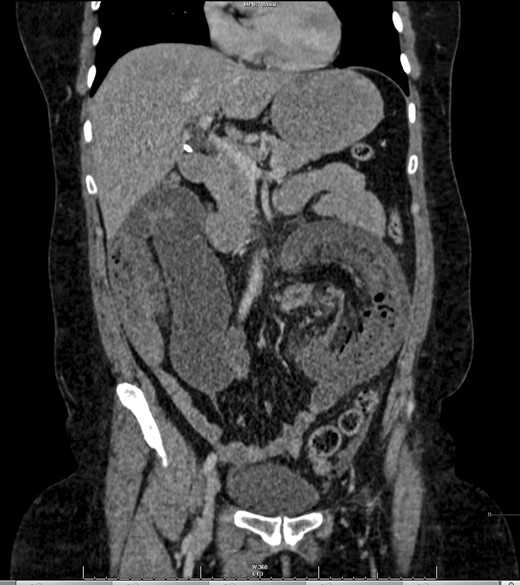

A 47-year-old female presented as an emergency with severe abdominal pain and profuse vomiting. She had been experiencing symptoms of intermittent vague abdominal pain associated with weight loss over 6 months, but no change in bowel habit. She had no significant past medical history. On examination she was tachycardiac, pyrexial and abdominal examination revealed distended abdomen with localized tenderness in the left iliac fossa. Blood tests revealed an elevated white cell count (18.8), C-reactive protein (25), microcytic anaemia (Hb 108) and a mildly raised lactate (2.37). She was commenced on intravenous fluids. An abdominal plain film showed prominent bowel loops and ultrasound of the abdomen revealed numerous loops of a distended, fluid filled, non-peristalsing bowel. There was some evidence of bowel wall thickening, but no clear source of obstruction was identified. A CT scan was performed showing mesenteric vascular gas and a target sign, virtually pathognomonic of intussuception [5, 6] (Figs 1 and 2).

The patient underwent a laparotomy, which revealed small bowel obstruction with evidence of impending perforation. A pedunculated polypoid lesion at the jejuno-ileal junction was identified as the lead point for intussusception. The intussuscepted segment of small bowel was resected and end-to-end primary anastomosis formed.

While correct diagnosis is based on operative findings, suspicion may be raised following imaging techniques. CT with both oral and intravenous contrast is now widely recognized as the most accurate diagnostic tool (58–100% accuracy in a recent case series) [1, 4]. Alternating hyper- and hypodense layers of the bowel wall of the intussuscepted segment give rise to a classical ‘target sign’ [5] (Fig. 1).